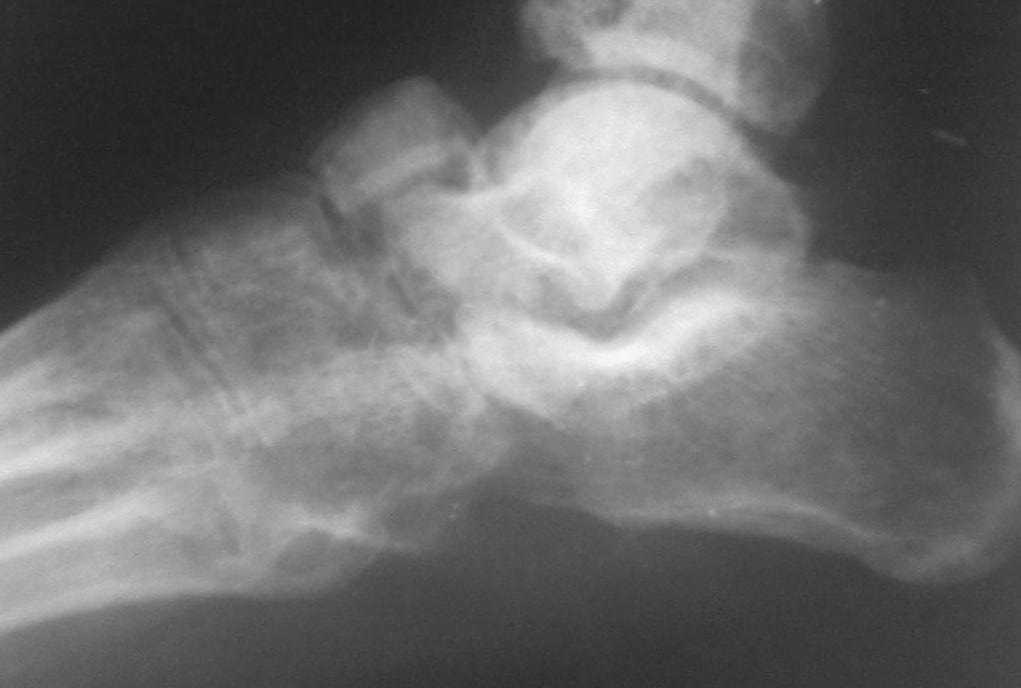

Обратился больной 46 лет. 3 месяца назад получил травму левой стопы в результате ДТП, живет в отдаленный степной зоне, лечился у местного табиба. Ходит при помощи двух костылей, наступая на пятку, на передный отд стопы наступать не может из-за боли, умеренная отечность стопы и деформация в обл. ладьевидной кости, движения в голеностопном суставе в польном обьеме, в средном отд ограничены и болезненны. Уважаемые коллеги, я пока не знаю что делать, помогите, пожалуйста, советами! С уважением Абдурашид.

По данному случаю, оказалось 3 месяца назад было произведена Р-графия в райбольнице, но больной предпочел лечится у табиба. Присылаю первичные снимки.

Да, наш с Вами диагноз, Абдурашид, подтвердился. Я бы предпочёл артродез, фиксация- в самом простом варианте-винтами 3,5 или 4,5 . Отломок послужит аутотрансплантатом. Плюс внешняя иммобилизация. С уважением, Волна